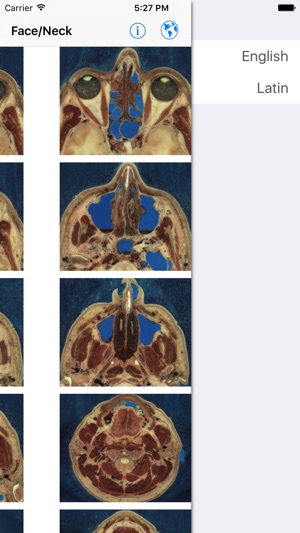

‎WINNER: NLM "Show Off Your Apps" iAnatomy: A simple, portable anatomy atlas of the face, neck, chest, abdomen, and pelvis. -75 images with 60 actual CT scans of the chest, abdomen, and pelvis -Cadaveric images of the face and neck -Separate male and female pelvis -Over 1300 anatomy identifying labe…